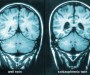

Further Readings On Lobotomy

Today in class, we viewed the PBS American Experience special on Dr. Walter Freeman. The PBS website has a ton of resources on it, including a 1946 article from Life Magazine that is absolutely heartbreaking and shocking to read. For some stories of those who were lobotomized at Pilgrim State mental hospital in New York, check […]